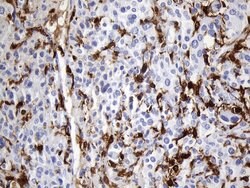

F13A1 Mouse anti-Human, Clone: UMAB243, liquid, UltraMAB™

This gene encodes the coagulation factor XIII A subunit. Coagulation factor XIII is the last zymogen to become activated in the blood coagulation cascade. Plasma factor XIII is a heterotetramer composed of 2 A subunits and 2 B subunits. The A subunits have catalytic function, and the B subunits do not have enzymatic activity and may serve as plasma carrier molecules. Platelet factor XIII is comprised only of 2 A subunits, which are identical to those of plasma origin. Upon cleavage of the activation peptide by thrombin and in the presence of calcium ion, the plasma factor XIII dissociates its B subunits and yields the same active enzyme, factor XIIIa, as platelet factor XIII. This enzyme acts as a transglutaminase to catalyze the formation of gamma-glutamyl-epsilon-lysine crosslinking between fibrin molecules, thus stabilizing the fibrin clot. It also crosslinks alpha-2-plasmin inhibitor, or fibronectin, to the alpha chains of fibrin. Factor XIII deficiency is classified into two categories: type I deficiency, characterized by the lack of both the A and B subunits; and type II deficiency, characterized by the lack of the A subunit alone. These defects can result in a lifelong bleeding tendency, defective wound healing, and habitual abortion.Specifications

| Immunohistochemistry (Paraffin) | |